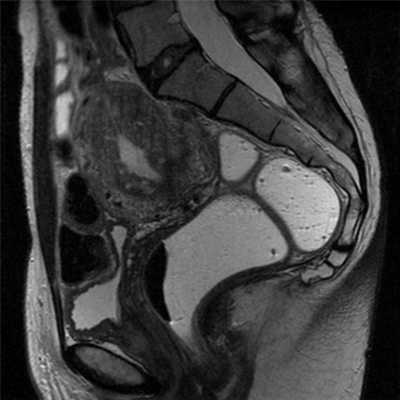

Аденомиоз выглядит как утолщение соединительной зоны образующее плохо отграниченную область низкой интенсивности сигнала, часто с гиперинтенсивными очагами на Т2-взвешенных изображениях. В основном локализуется в области дна, и, как правило, в задней стенке матки.

Выделяют две формы аденомиоза (рис.3):

1) диффузная: очаги аденомиоза распределены в пределах всего миометрия.

2) фокальная: очаги аденомиоза в миометрии присутствуют на ограниченном участке.Наиболее важным для диагностики аденомиоза признаком на МРТ является толщина переходной зоны более 12 мм. Толщина менее 8 мм, как правило, позволяет исключить диагноз.

При толщине переходной зоны от 8 до 12 мм, диагноз аденомиоза требует определенных вторичных критериев.

МРТ признаки аденомиоза:

![]()

Рис.3: Схематическое изображение и сагиттальные T2-взвешенные изображения нормальной постпубертатной матки (а), диффузного аденомиоза (b), фокального аденомиоза (с).

а) эндометрий однородно гиперинтенсивный, тонкая переходная зона имеет низкую интенсивность сигнала, наружный миометрий имеет промежуточную интенсивность сигнала; b) и с) аденомиоз матки с гипонтенсивным диффузным и фокальным расширением переходной зоны.